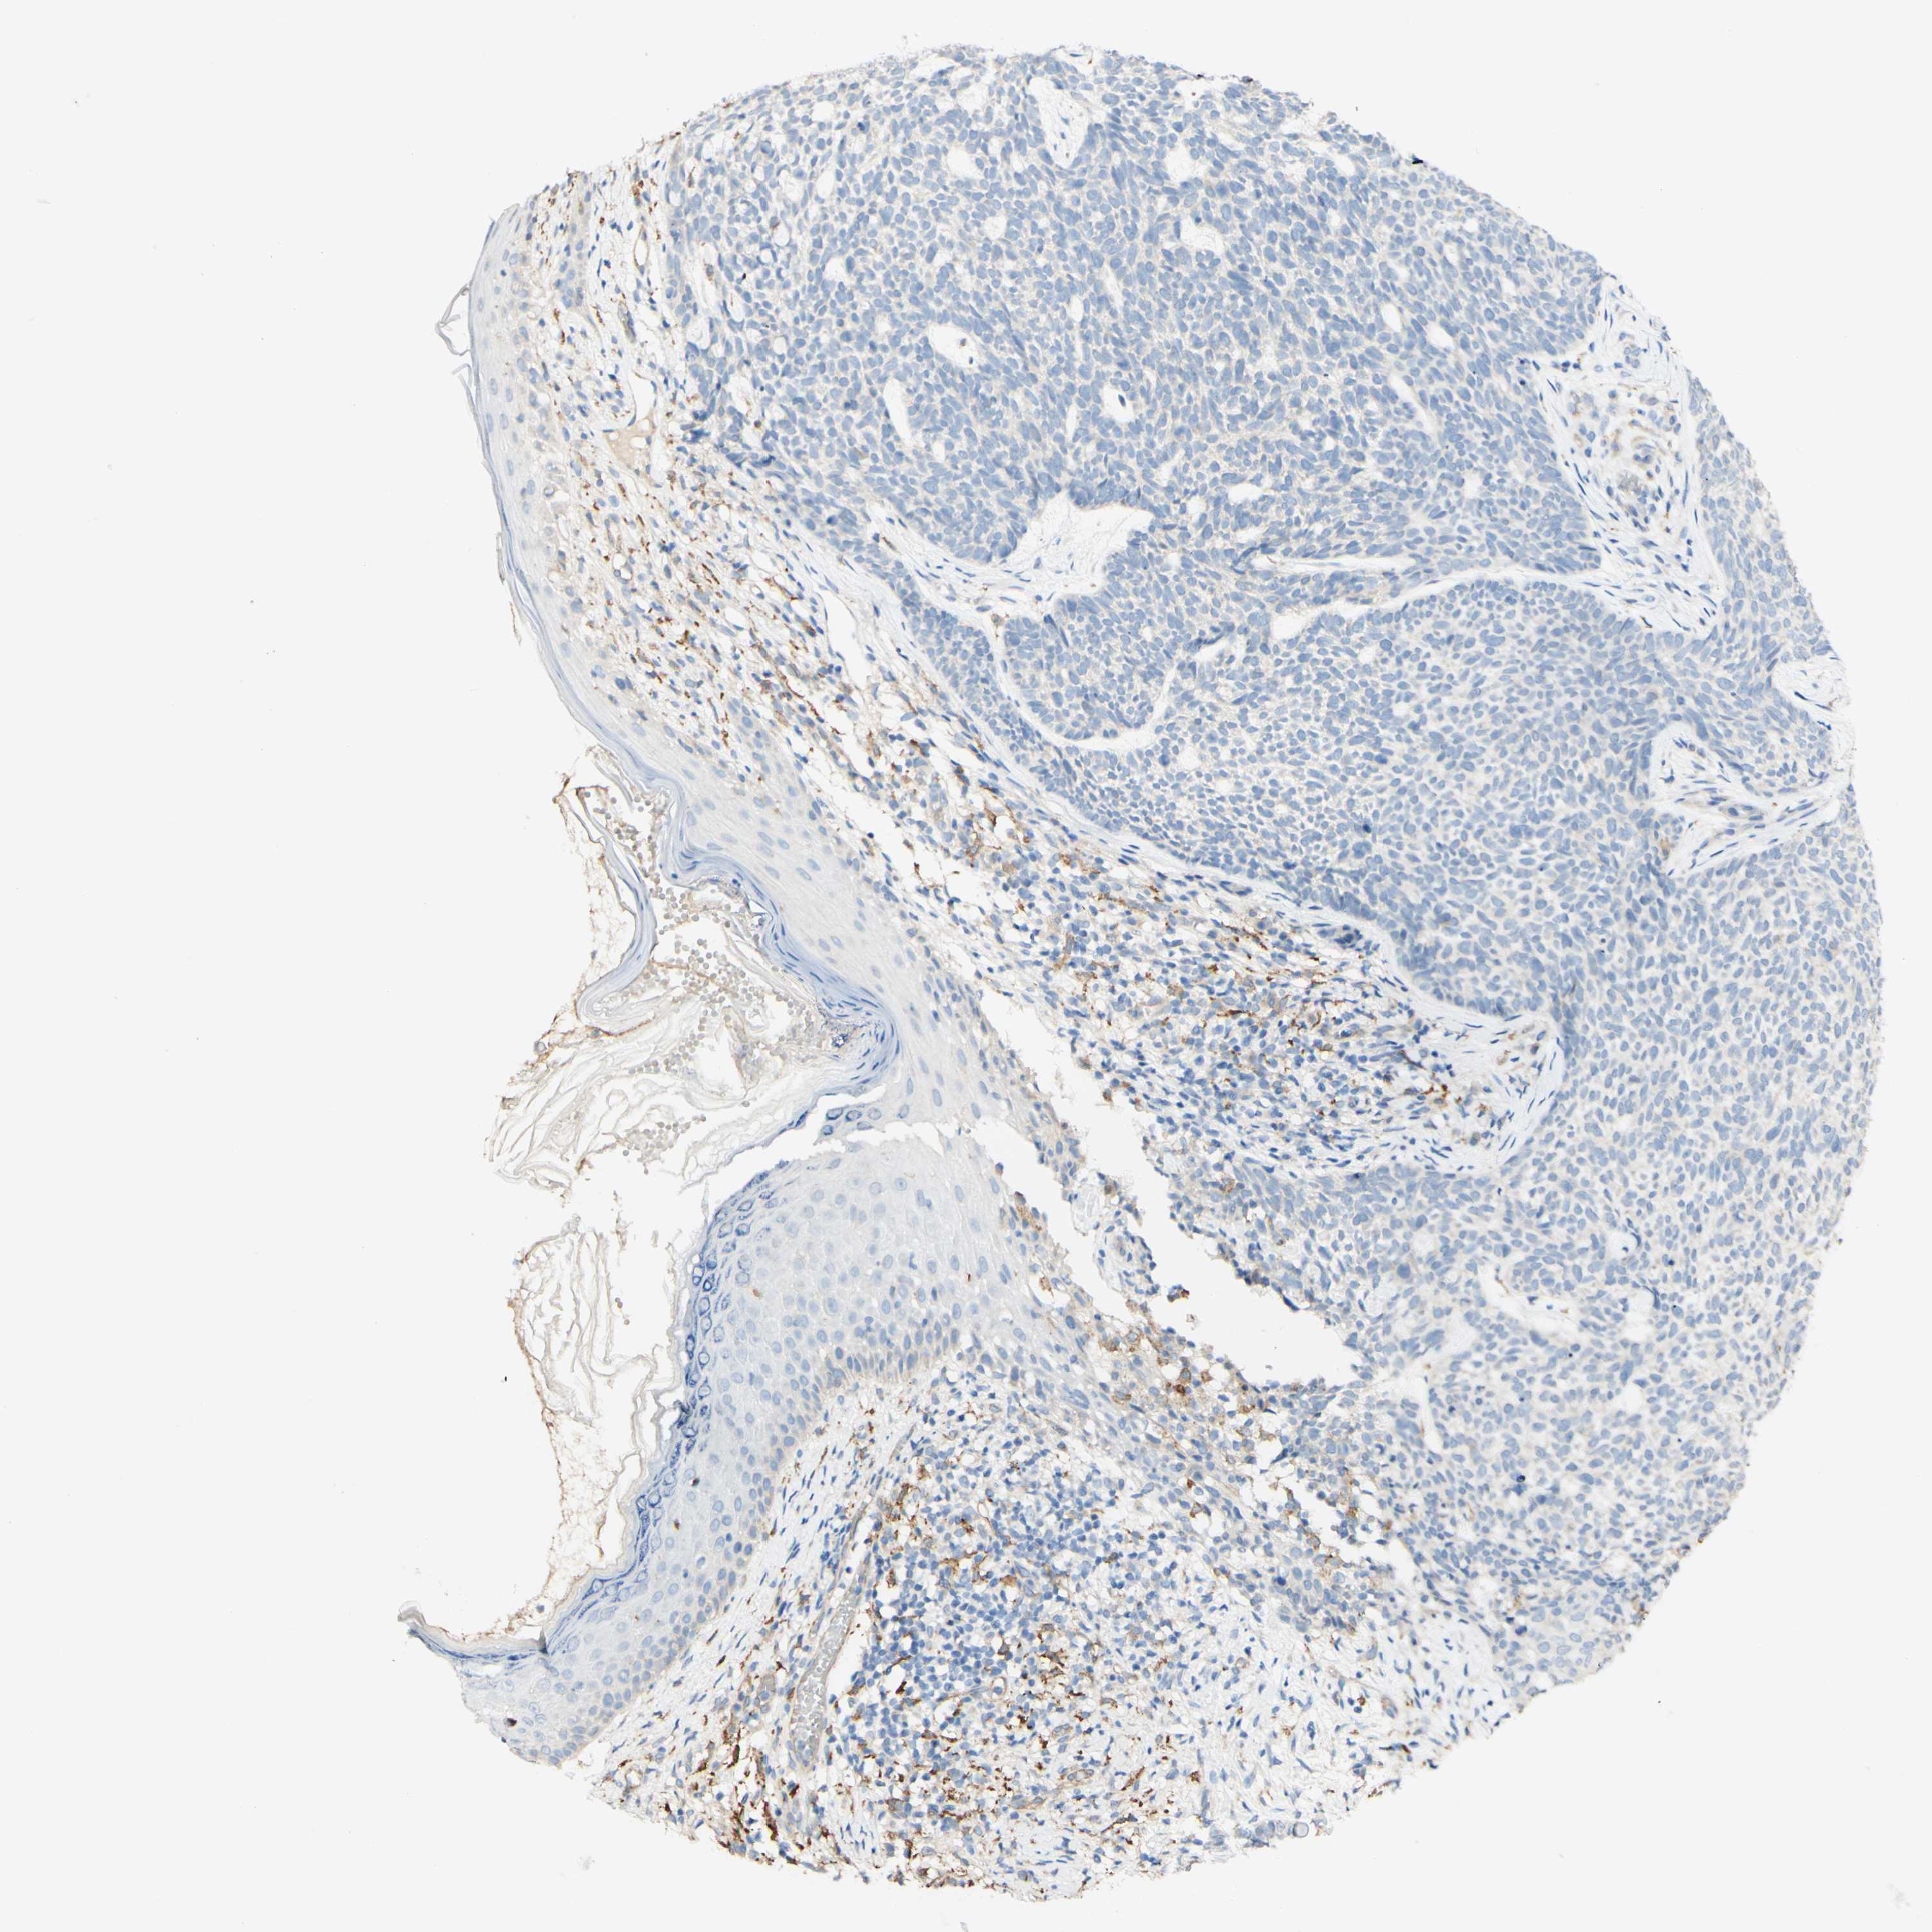

CANCER SKIN CANCER Show tissue menu

SKIN CANCER - Protein expressioni

A mouse-over function shows sample information and annotation data. Click on an image to view it in a full screen mode. Samples can be filtered based on level of antibody staining by selecting one or several of the following categories: high, medium, low and not detected. The assay and annotation is described here.

Each image is clickable and will lead to virtual microscopy that enables deeper exploration of all samples and also displays staining intensity scores, fraction scores and subcellular localization as well as patient and tissue information for each sample.

Antibody HPA015130

Basal cell carcinoma

Squamous cell carcinoma in situ, NOS

Squamous cell carcinoma, NOS